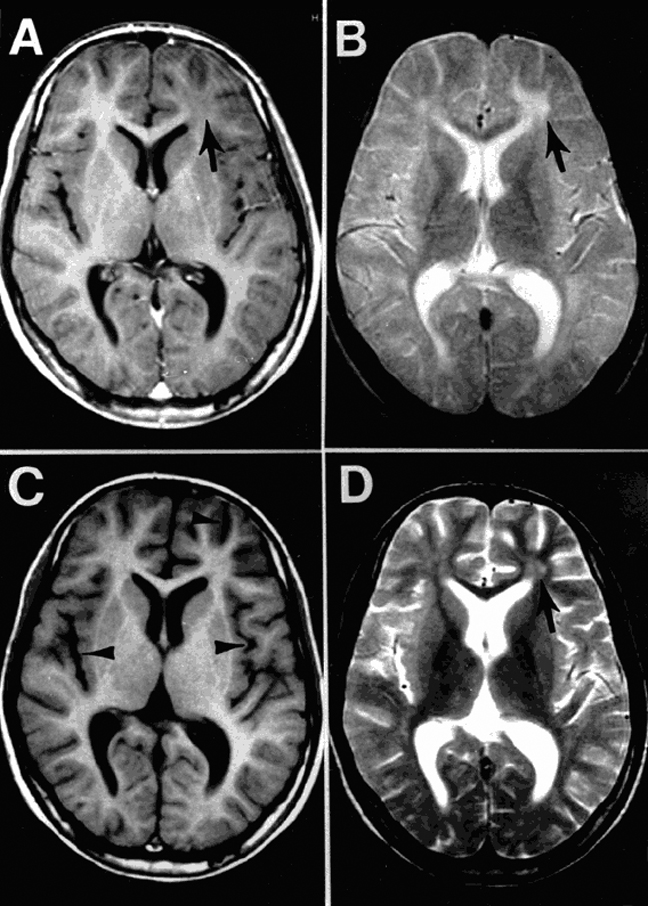

Subakute sklerosierende Panenzephalitis bei Einweisung (A, B) und drei Monate später (C, D). Es besteht eine Anomalie im linken Frontallappen (Pfeil in A, B, D) sowie eine diffuse Atrophie im Kortex (Pfeile in C). Subakute sklerosierende Panenzephalitis bei Einweisung (A, B) und drei Monate später (C, D). Es besteht eine Anomalie im linken Frontallappen (Pfeil in A, B, D) sowie eine diffuse Atrophie im Kortex (Pfeile in C). © wikimedia/Bonthius D, Stanek N, Grose C/CDC